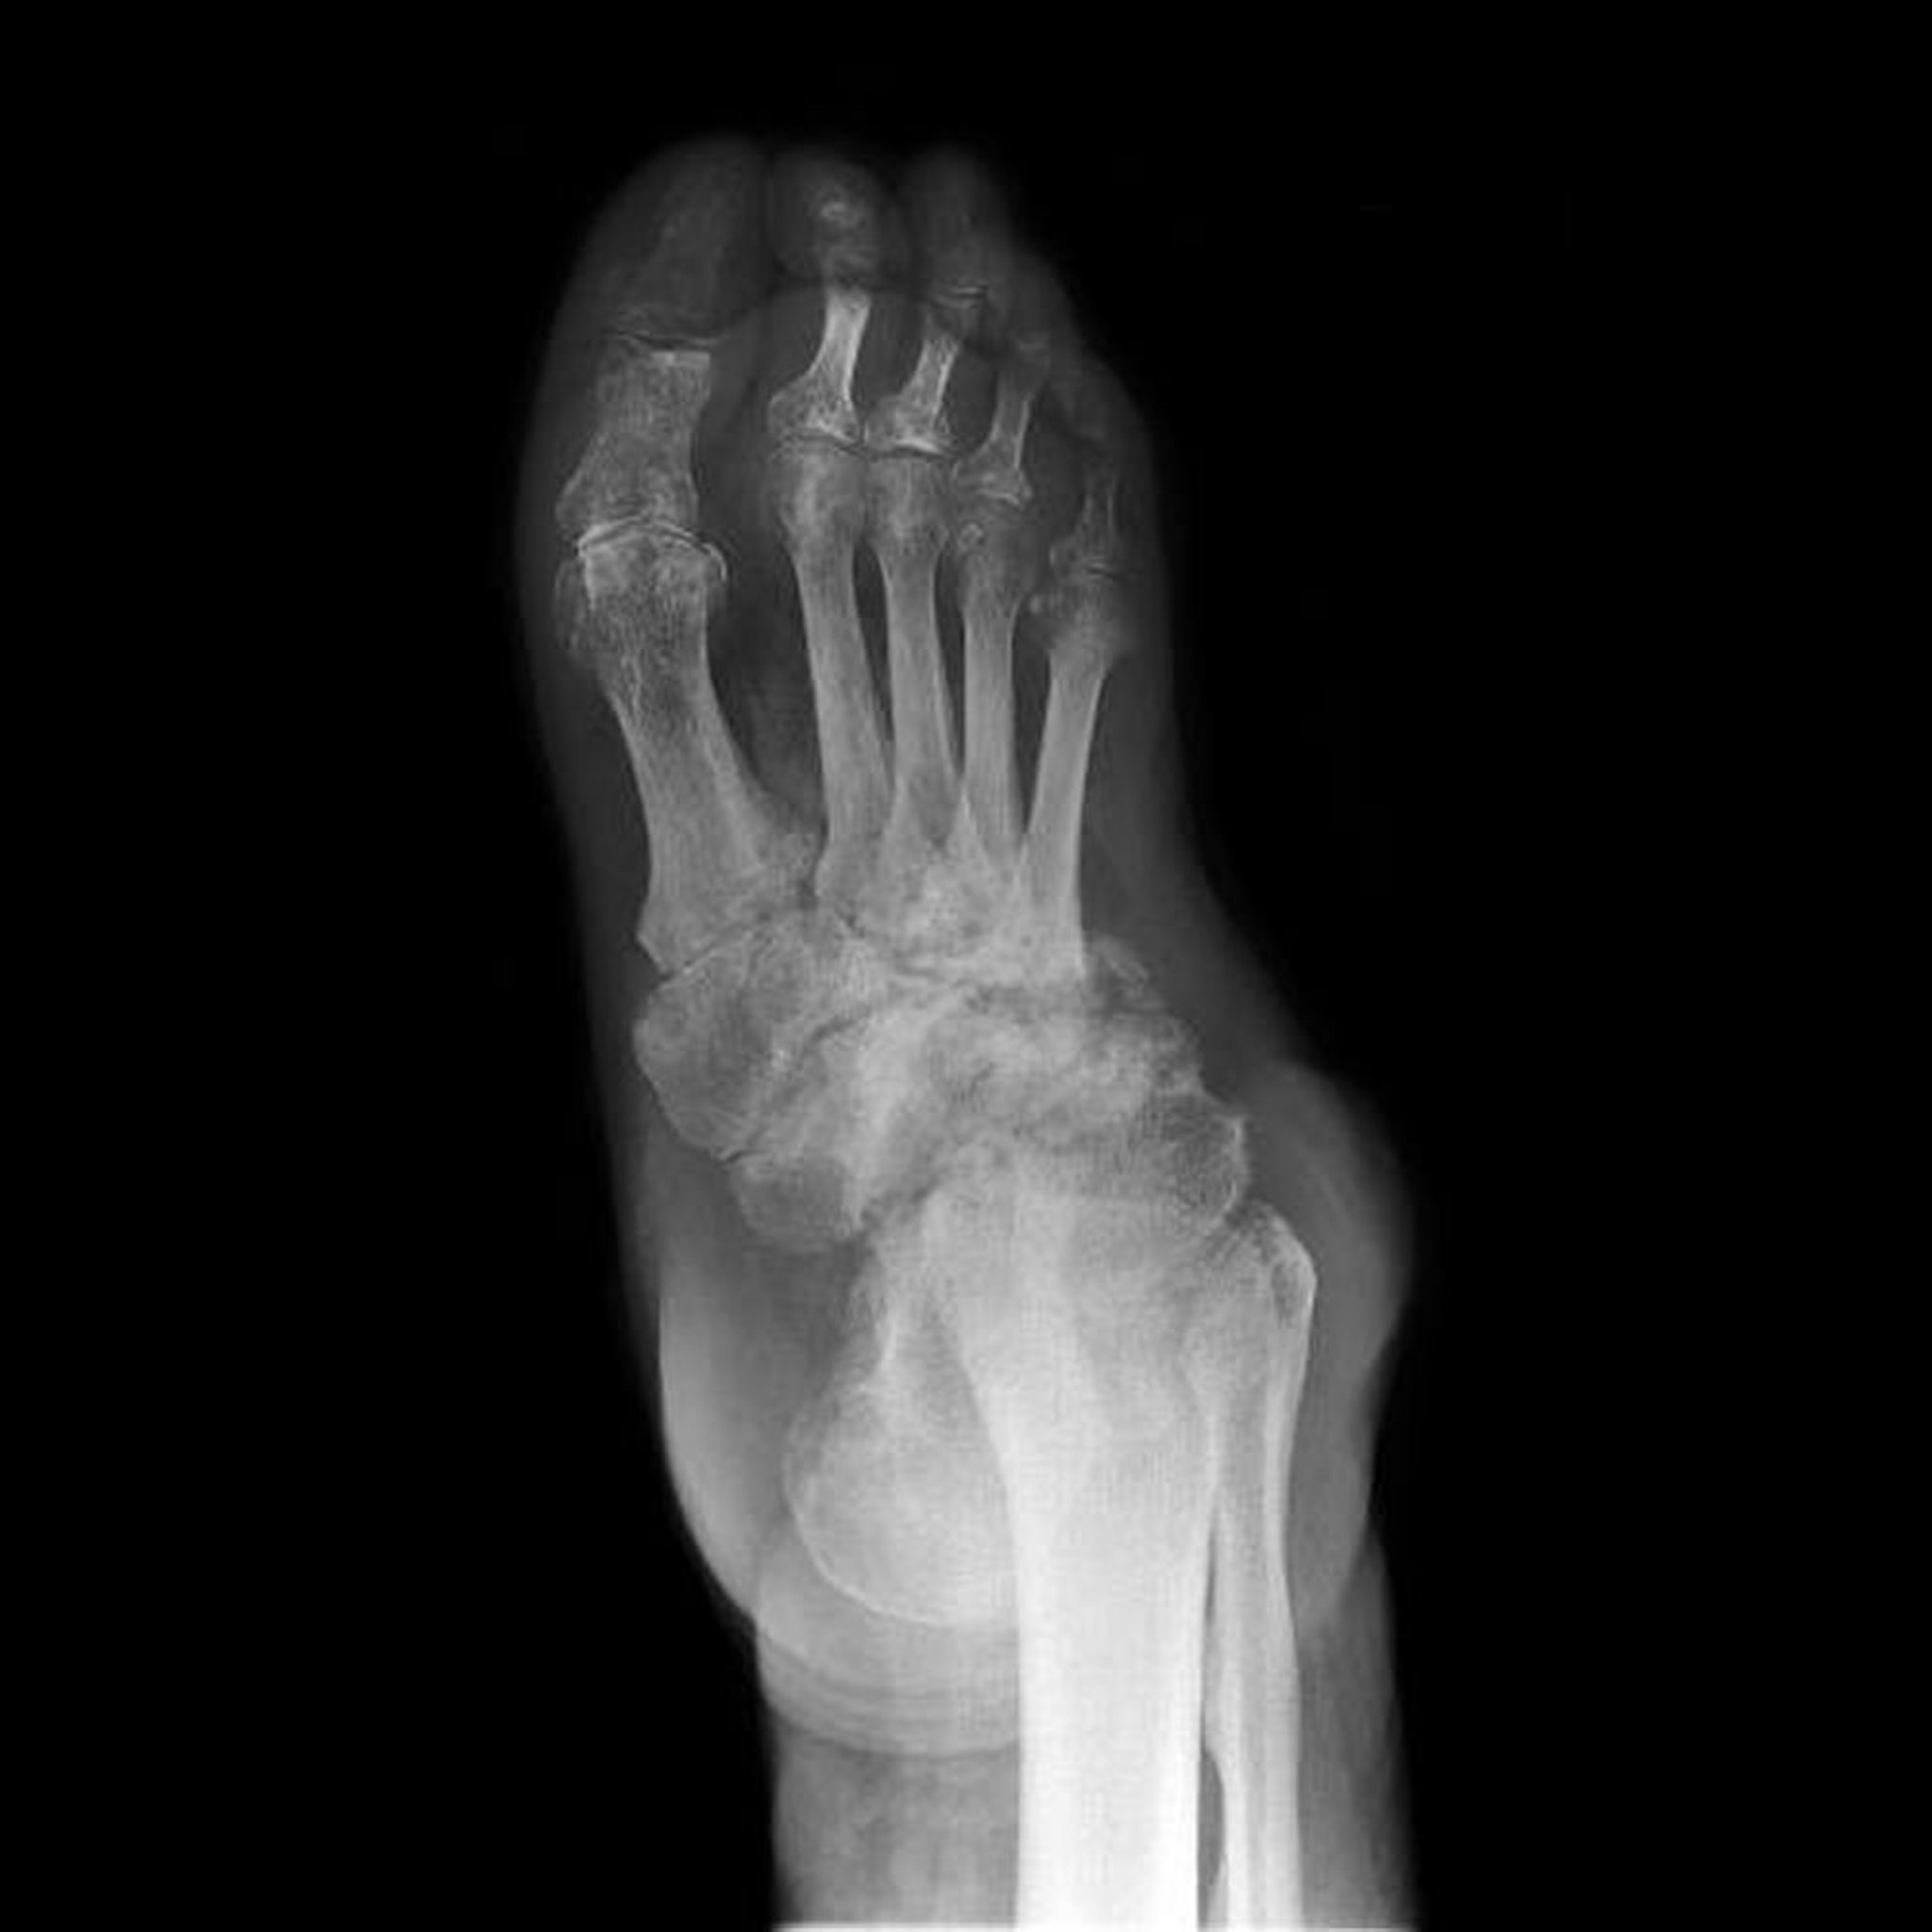

Artropatia neuropática do pé

Essa radiografia mostra artropatia neuropática do pé (também conhecida como pé de Charcot). A destruição, as deformidades e a perda dos espaços articulares dos ossos do tarso são extensas.